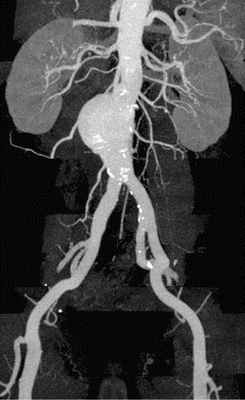

На основании серии поперечных срезов на рабочей станции выполнялись многоплоскостные и объемные реконструкции. По данным ЭЛТ, сразу за кольцом аортального клапана, диаметр которого составлял 3.0 см, начинается аневризматическое расширение восходящей аорты, достигающее 6.3 см в диаметре на границе между проксимальной и средней ее третями. Диаметр дуги аорты 3.5 см, нисходящей аорты - 3.3 см. Начиная от уровня синусов Вальсальвы, видна отслоившаяся интима, имеющая извитой ход и формирующая ложный канал вдоль задне-левой стенки аорты (рис. 6 а, b, с). Расслоение переходит на дугу аорты и заканчивается в ее дистальной трети. В нижней части отслоившейся интимы видна фенестрация размером около 2.5 см; в дистальном отделе дуги имеется второй разрыв интимы диаметром около 2.0 см. Тромботические массы в просвете ложного канала отсутствуют. При анализе состояния сосудов, отходящих от дуги аорты, обнаружен переход расслоения на устье брахиоцефального ствола.

Таким образом, данные ЭЛТ также свидетельствуют о наличии аневризмы восходящей аорты и ее расслоении (II тип) с вовлечением устья брахиоцефального ствола.

Рис. 6. Электронно-лучевая томография.

а - срез в поперечной плоскости. В просвете аорты, заполненном контрастным препаратом, видна отслоившаяся интима,

b - реконструкция в сагиттальной плоскости. Визуализируется проксимальный разрыв отслоившейся интимы,

с - трехмерная реконструкция.

Fig. 6. Electron-beam СТ.

а - cross section. The detached intima can be observed in the aortic lumen filled with a contrast agent,

b - reconstruction in the sagittal plane. Proximal rupture of the detached intima can be visualized,

с - three-dimensional reconstruction.